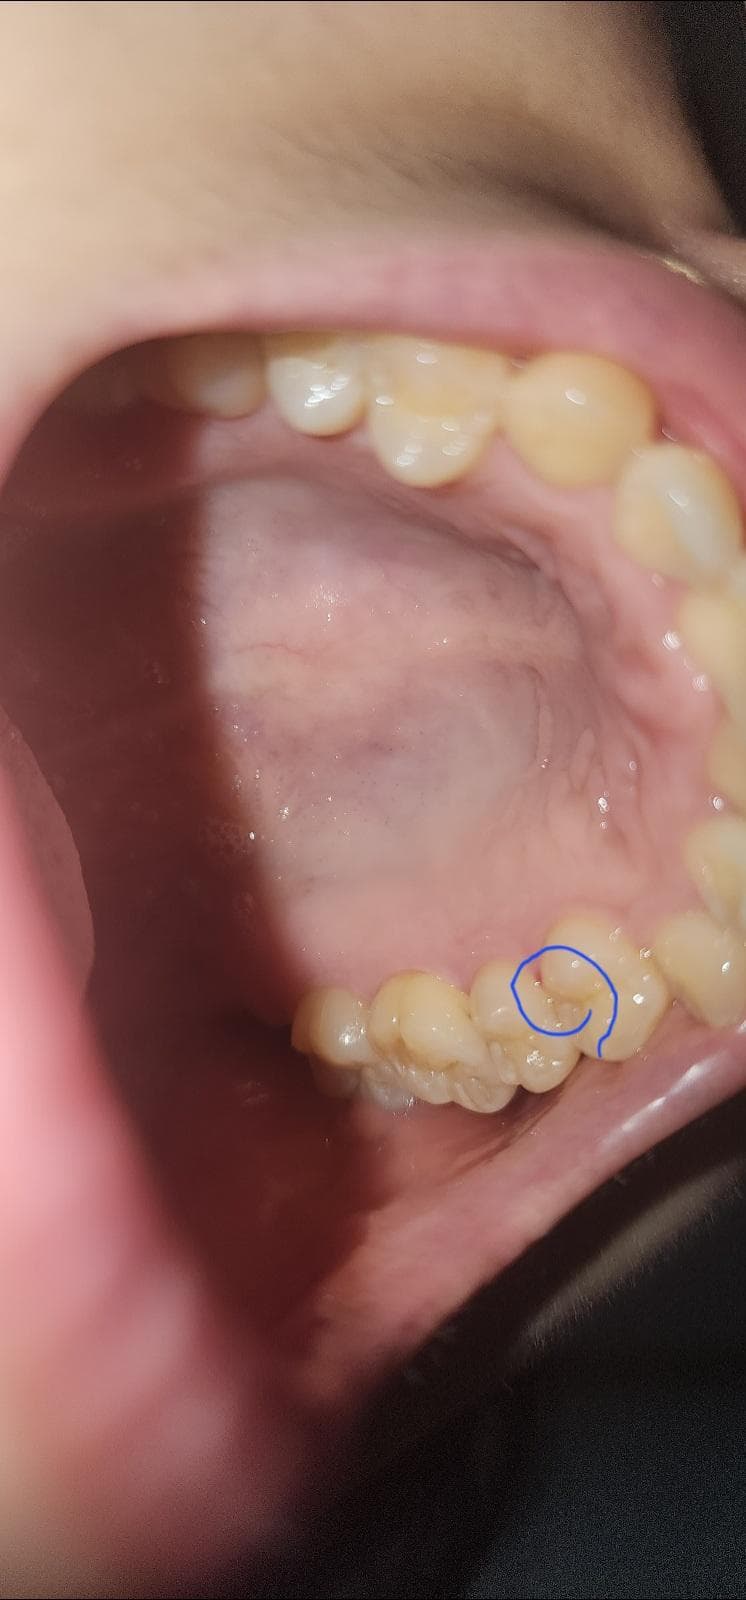

치과에서 잇몸치료후 치위생사가 치아 사이에 치간칫솔 사용해서 2~3회 왕복을 하며 치간칫솔 사용 방법을 알려줬어요 그러고 난뒤 피가 나거나 붓거나 고름이 나오는 증상은 없지만 계속 따가운 느낌이 들어 사진을 찍어보니 어금니 사이 잇몸이 파랗게 동그라미친 부분처럼 빨갛게 상처가 나있네요 이번주 화요일에 치료를 받았구요 계속 좀 불편하고 신경이 쓰이는데 괜찮아질까요? 어떻게 관리를 해야 할까요?